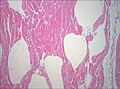

Biopsie de muscle examinée au microscope (colorée à l'haematoxyline-éosine, zoom 100×). Les vides blancs entre les fibres musculaires correspondent à des bulles de gaz.

Biopsie de muscle montrant une bactérie Gram-positive, anaérobie formant des endospores dans le muscle infecté, très compatible avec une infection à Clostridium perfringens.